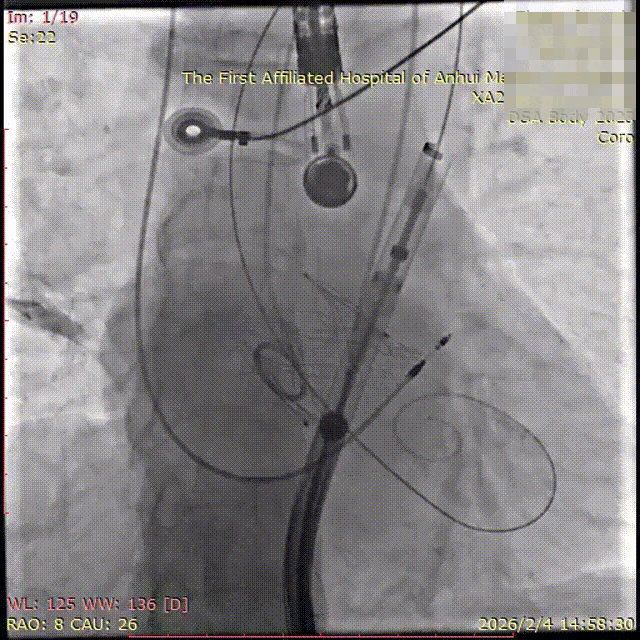

2026年伊始,TaurusTrio经导管主动脉瓣系统在武汉大学人民医院,中国科学技术大学附属第一医院,安徽医科大学第一附属医院,安徽医科大学第一附属医院北区,首都医科大学附属北京安贞医院南充医院,海南省人民医院等多家临床中心成功开展上市后全国首批植入。这不仅是TaurusTrio正式走向广泛临床应用的重要里程碑,更标志着中国单纯主动脉瓣反流介入治疗正式迈入了“心键合璧”的全新纪元。